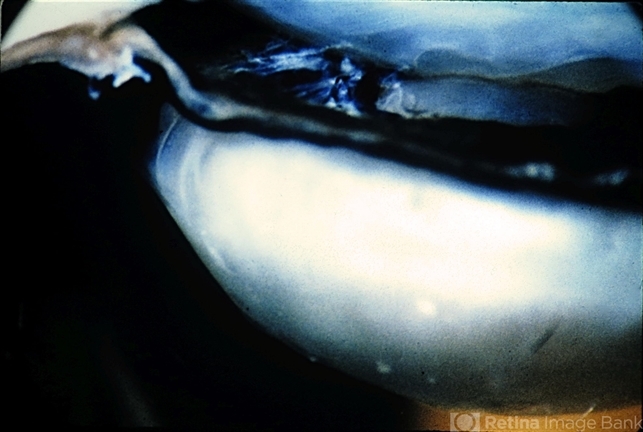

- iridoschisis

- lridoschisis. Macroscopic appearance of the same cases.